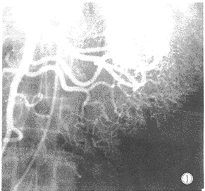

4.選擇性腸系膜動脈造影 可顯示腫瘤血管影,邊界多較清楚。出血量≥0.5ml/min時腸系膜動脈造影可顯示造影劑逸出血管外;出血停止或出血量<0.5ml/min時不能顯示造影劑外溢,但有可能發現血管豐富的腫瘤。